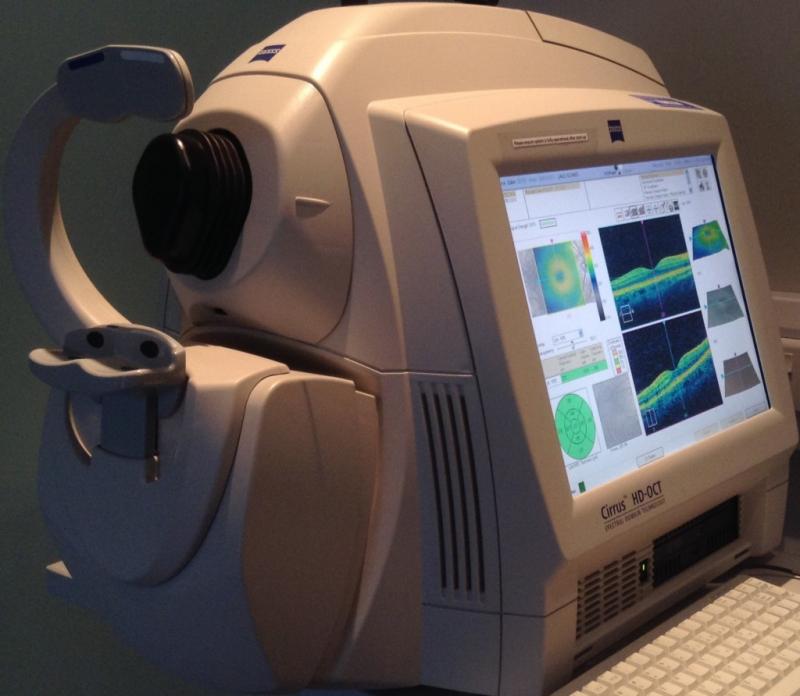

Диагностика зрения: Когерентная томография сетчатки